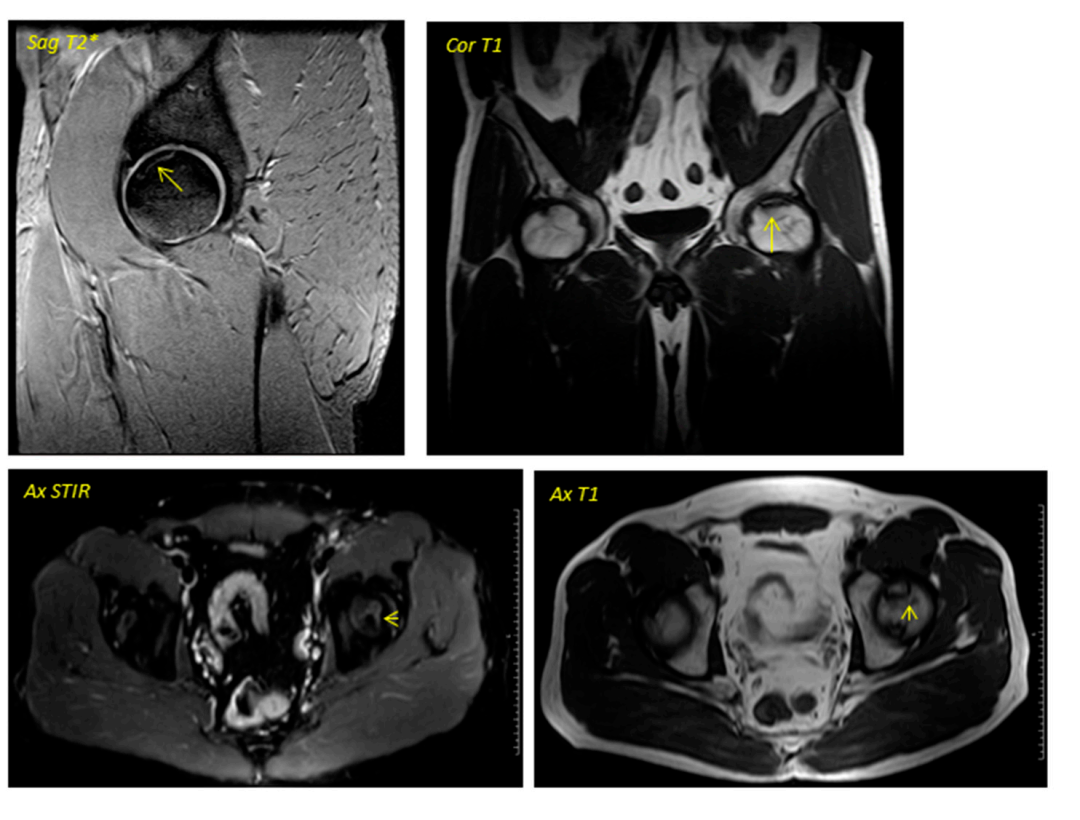

④影像学变化:在早期阶段变化并不明显,第6个月开始所有患者出现改变;62.5%的患者(n = 5)在手术后的一年内实现了影像学稳定(部分患者影像学图1、2)。

图2:图1中患者的术后磁共振成像2016年4月